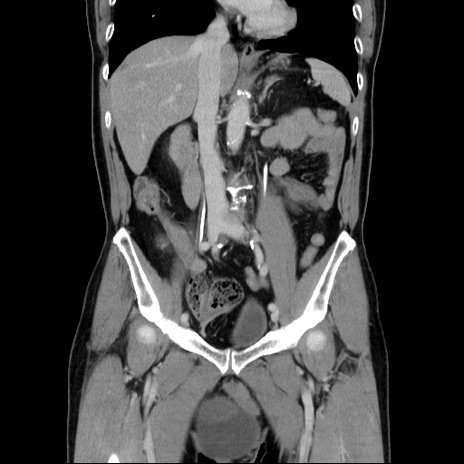

症例34(冠状断像)

【症例】60歳代 男性

【主訴】右鼠径部膨隆

【現病歴】1年程前より右鼠径部膨隆あり。自己にて還納可能だったため放置していた。3時間前より右鼠径部の脱出を認め、還納困難となり受診。

【既往歴】高血圧

【身体所見】右鼠径部に小児頭大の膨隆あり。弾性硬であり、用手還納は困難。左鼠径部にも膨隆を認める。脱出はなし。

【データ】WBC 15500、CRP 測定なし